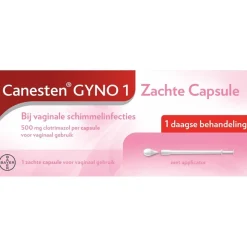

Gerelateerde producten

- Intieme Ongemakken